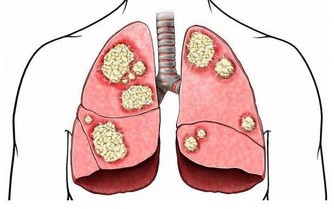

蛋白過多,死得越快。為什麼?很多氨基酸從尿裡排出,影響腎臟;消化不良,又會造成腸道毒素太多。

這也就罷了,關鍵是,孩子正餐還要吃很多肉。在臨床中,經常有幾歲的小女孩,過早乳房發育,甚至形成結節,均與飲食中過多肉蛋奶有很大關係,營養過剩,促使孩子過早發育,過早成熟。

對於成年人來說,大魚大肉,營養過剩,從而引起各種慢性疾病,被稱為“富貴病”,這就不用我贅述了吧?